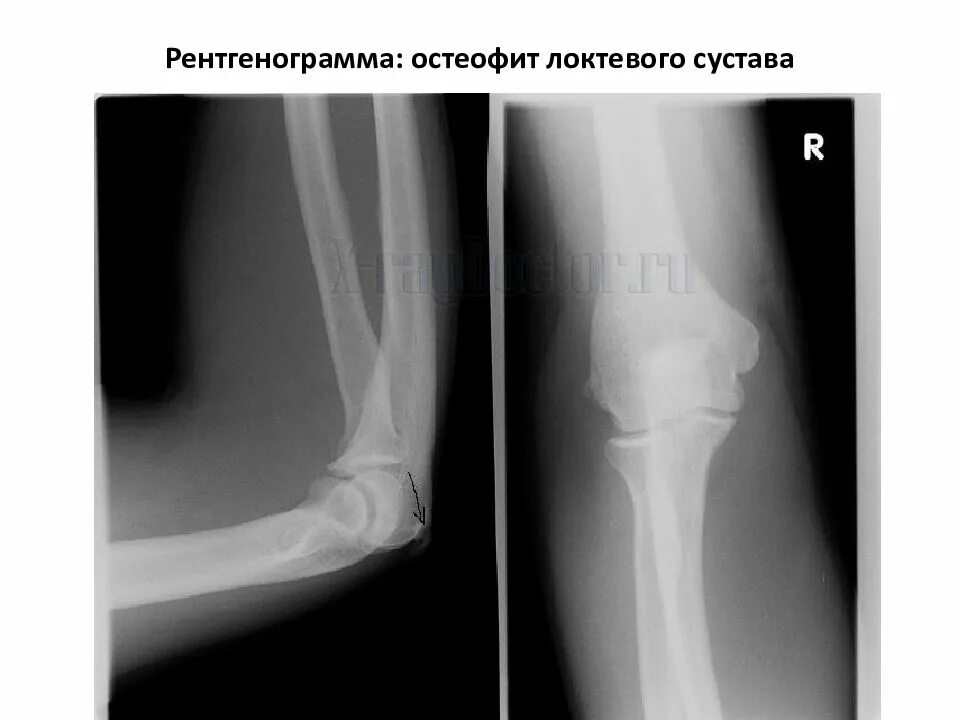

Суставная щель 3 3 мм